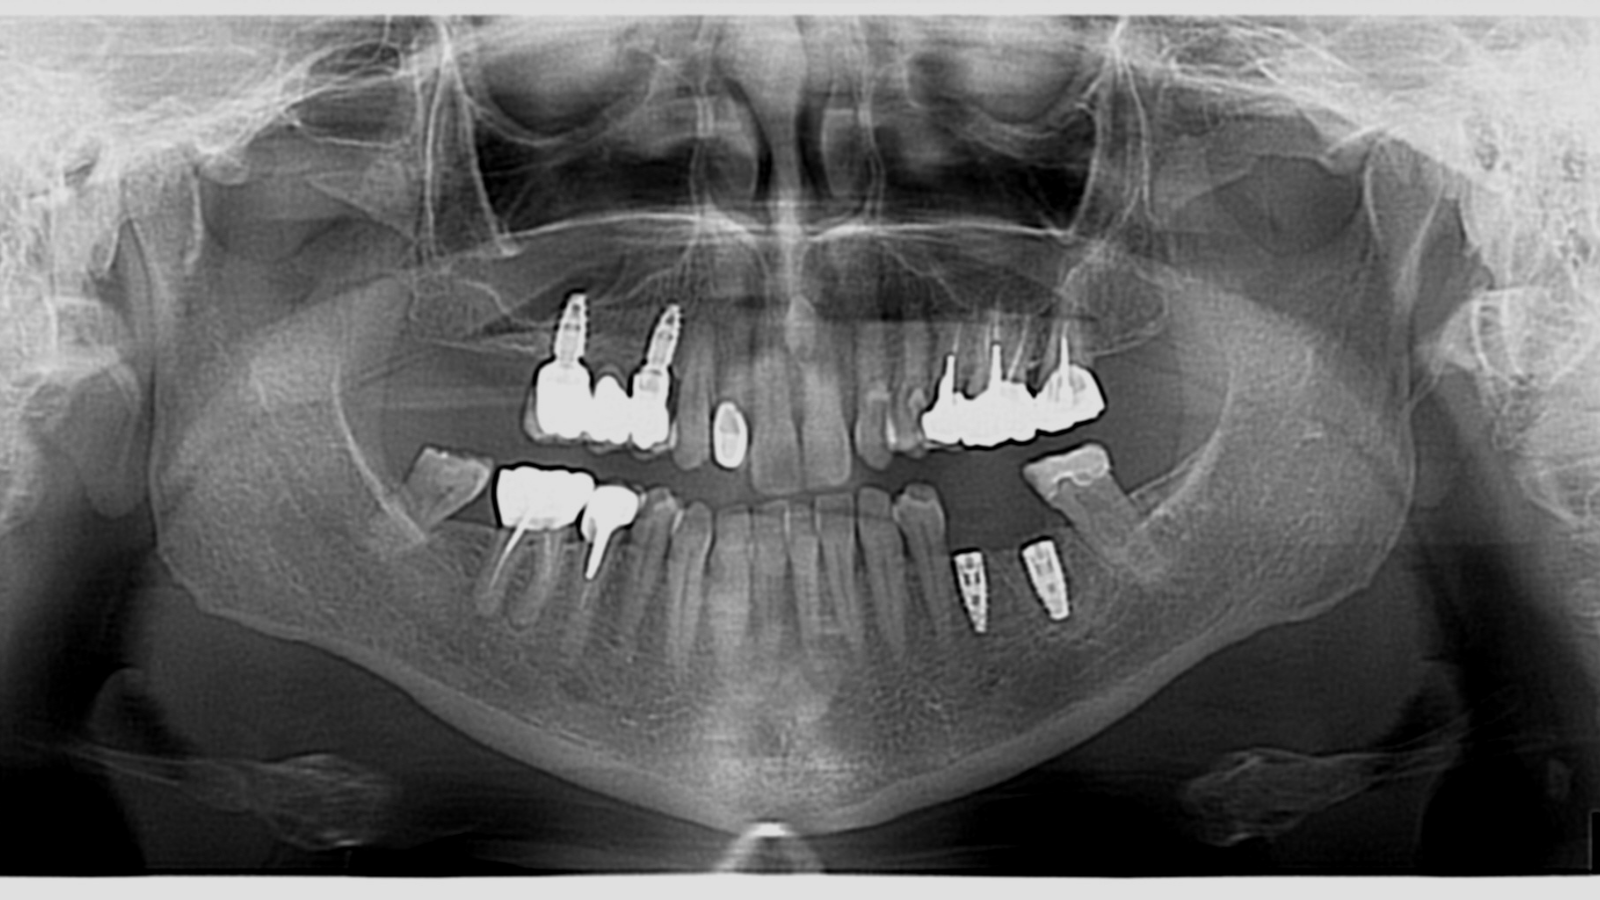

Kyste intra-osseux mandibulaire : extraction, énucléation et réhabilitation implantaire immédiate

Problème : kyste intra-osseux associé à la perte de toutes les dents de l’arcade inférieure.

Conduite à tenir (CAT) : extraction des dents restantes, énucléation du kyste, puis mise en place de 5 implants avec mise en charge immédiate, le tout réalisé en une seule séance.